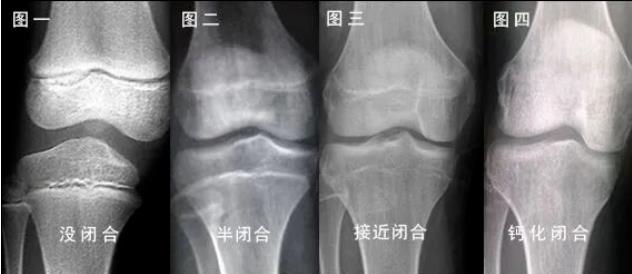

骨骺一旦闭合,亡羊补牢已经于事无补,骨骺闭合就没有任何办法了。

虽然不乏存在晚长的孩子,但现实是由于这种侥幸心理,很多孩子没有达到理想身高,甚至不及遗传身高。家长开始着急焦虑,但摆在眼前的是

身高生长停止的标志是骨骺和骨干

完全融合成长板消失

男童约为骨龄16岁女童约为骨龄14岁